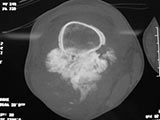

X-Rays:

- Lobulated and ossified exophytic mass (cauliflower-like) adjacent to the cortex; attached to metaphyseal cortex via a broad base

- Centrally, the tumor is radiodense (demonstrates ossification)

- Peripherally there may be small radiolucies that represent low grade cartilaginous lobules, fibrous tissue or fat

- The underlying cortex may be thickened

- There is no periosteal reaction since the tumor comes from the outer layer of the periosteum and therefore does not elevate the periosteum.

- Large tumors encircle the bone

- Appears to have broad attachment to underlying cortex with a cleft between exophytic base and cortex at periphery. This is referred to as a “String Sign” (cleft is often only identifiable on CT scan)

- There may be invasion of the medullary canal with long standing disease

- High grade or defifferentiated areas may appear as large radiolucent areas/mass adjacent to radiodense areas